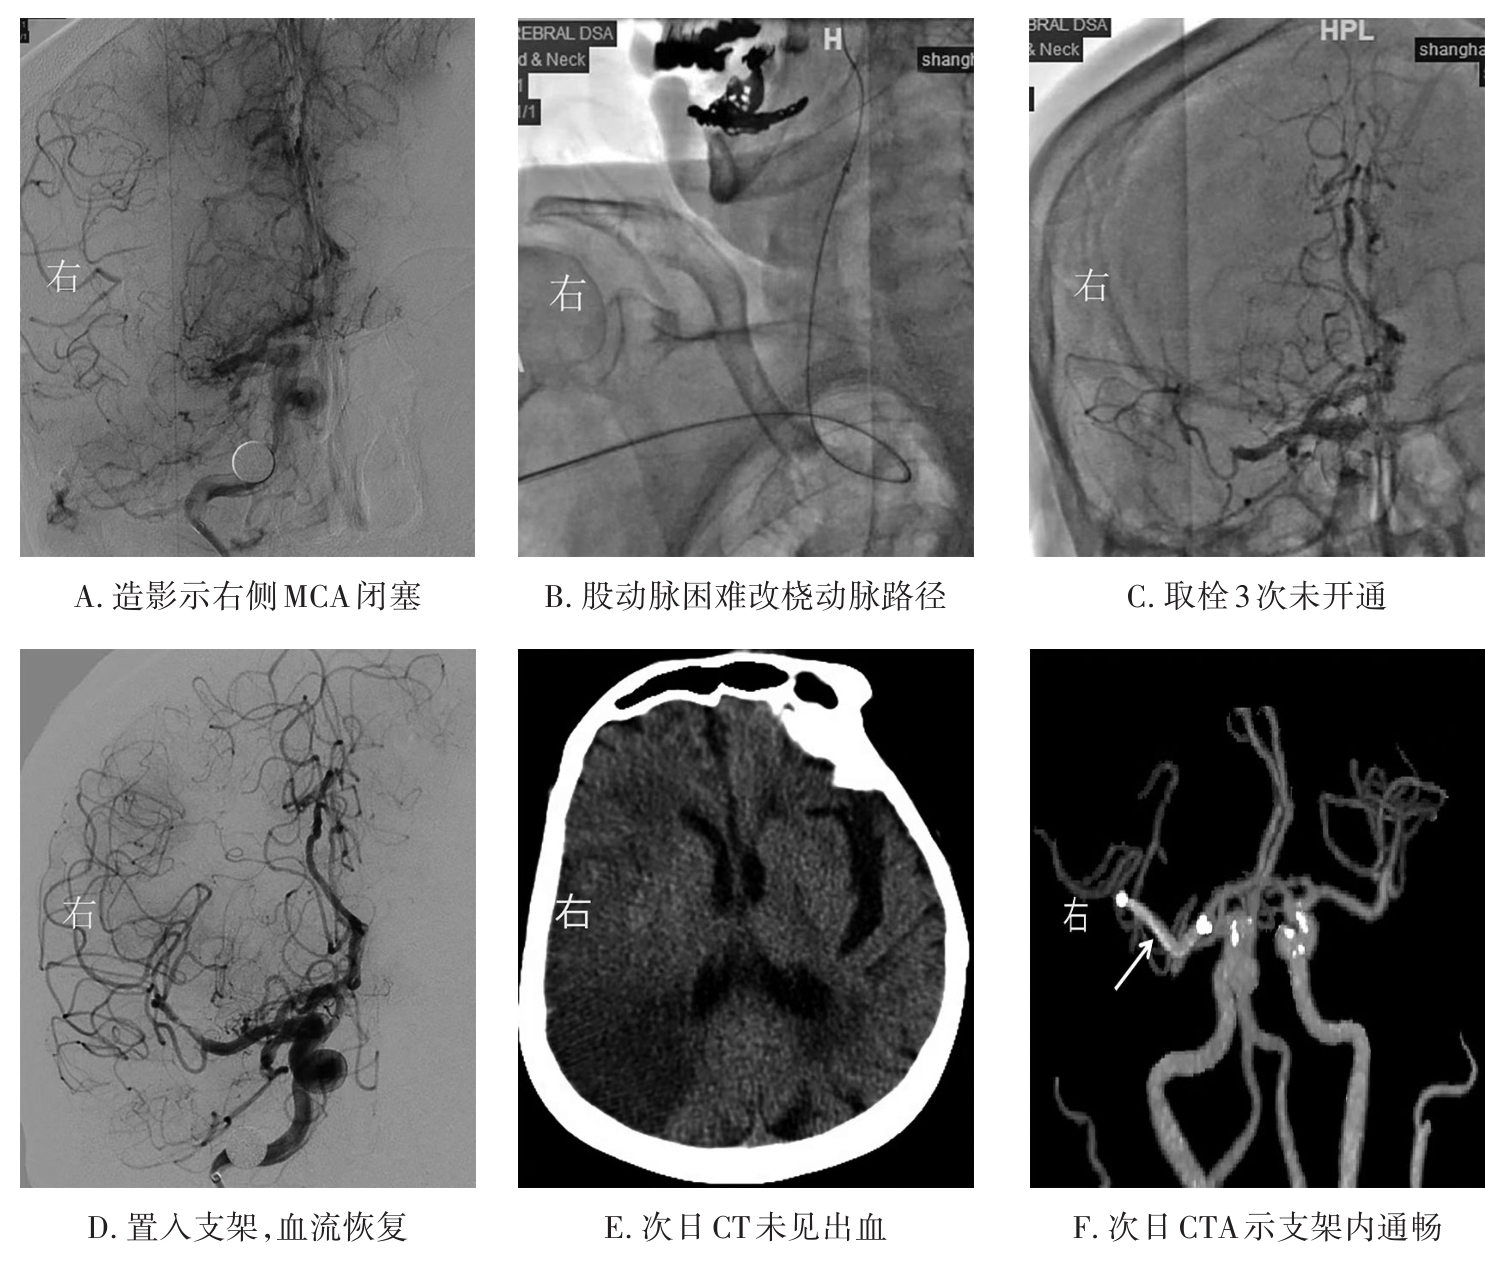

• 挽救性支架植入对取栓困难的脑动脉栓塞开通效果

摘要:目的 探究急性脑栓塞取栓失败和神经介入术中发生医源性脑动脉栓塞后补救性支架植入术的开通效果。方法 回顾性分析2020年1月至2021年11月上海交通大学医学院附属第九人民医院6例脑栓塞取栓失败和4例医源性颅内中远端动脉栓塞、接受补救性支架植入术的患者临床信息,总结患者术后血管开通情况、术后24 h 支架内血流通畅情况、出血转化和预后等情况。结果 6例急性脑栓塞取栓失败,补救性支架植入后闭塞血管全部开通(modified thrombosis in cerebral infarction score,mTICI 2b~3),术后3例出血转化(1例PH2型,2例HI2型),术后24 h支架内血流通畅5例(83%),1例未行血管造影复查;3例患者住院期间死亡。4例医源性中远端动脉闭塞中,1例为原发病为椎基底动脉高度狭窄,支架置入术中发生右侧小脑前下动脉闭塞,补救性支架置入后完全开通,术后24 h复查所有支架通畅,无脑出血,3个月预后良好,改良Rankin量表(modified Rankin score,mRS)评分1分;3例原发病为大脑中动脉栓塞,取栓术中出现同侧大脑前动脉分支闭塞,补救性支架植入后完全开通,其中1例术后24 h头颅计算机体层血管成像(computed tomography angiography,CTA)可见支架通畅,合并片状出血转化(HI2型),2例因为病重未行血管复查。结论 补救性支架植入可以快速开通取栓失败以及医源性中远端动脉的栓塞,但是疗效和安全性需进一步研究。